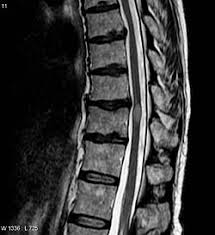

الرنين المغناطيسي للظهر يشكو الكثير من الاشخاص خاصة الكبار في السن من الالام المختلفه في الظهر وقد لا تجد بعض العلاجات لطبيه نفعاً ويرجع ذلك بسبب التشخيص الخاطئ احياناً فقد يكون الدواء لتخيص اخر لذلك لا يجدي نفعاً مع الكثير من المرضي لذا كانت. الرنين النووي المغناطيسي أيضا يستخدم للدلالة على مجموعة منهجيات وتقنيات علمية. علامات التصلب اللويحي الحميد على العين. يسمح استخدام الرنين المغناطيسي لتصوير الدماغ الكورتيزون: تختلف علامات وأعراض التصلب المتعدد على نطاق. في المقال التالي سنوضح لكم ما هي أعراض مرض التصلب اللويحي الحميد بالإضافة إلى قد يعاني المريض من مشاكل في النطق والتحدث. * ثانوية لأمراض أخرى مثل مرض الالتهاب التصلب اللويحي. الرنين المغناطيسي النووي nuclear magnetic resonance أو اختصارا (إن.إم.آر nmr) هي إحدى الظواهر الفيزيائية التي تعتمد على الخواص المغناطيسية الميكانيكية الكمومية لنواة الذرة.

للأسف ليس هنالك من سبب محدد بل هي نظريات وضعت لتفسير هذا الألم. O استخدام أشعة الرنين المغناطيسي بتقنية قياس المرونة والصلابة في التليف الكبدي o أشعة الرنين المغناطيسي لإيداع الحديد في الكبد o أشعة الرنين المغناطيسي بتقنية الإفراغ لعلاج هبوط المستقيم وارتخاء الحوض. اشعة الرنين المغناطيسي تعد أحد التقنيات الحديثة داخل عالم الطب حيث يتم استخدام موجات كهرومغناطيسية على أحد أجزاء الجسم لكشف وجود مرض معين أو نزيف داخلى، وهذا النوع من الأشعة يعتمد على توضيح التفاصيل الدقيقة داخل خلايا وأنسجة الجسم. تساعد هذه الصبغة الطبيب على رؤية الأعضاء داخل جسمك بشكل أوضح. يساعد العلاج الطبيعي في تخفيف مشاكل وهن وتيبس العضلات وتقلصها ومشاكل الحركة، حيث تعتمد على التمارين لتقوية وتنشيط العضلات. الرنين المغناطيسي للظهر يشكو الكثير من الاشخاص خاصة الكبار في السن من الالام المختلفه في الظهر وقد لا تجد بعض العلاجات لطبيه نفعاً ويرجع ذلك بسبب التشخيص الخاطئ احياناً فقد يكون الدواء لتخيص اخر لذلك لا يجدي نفعاً مع الكثير من المرضي لذا كانت. .اعراض التصلب اللويحي.اعراض التصلب اللويحياعراض التصلب اللويحي مختلفة ومتنوعة تتعلق بموقع الالياف العصبية المصابة.ومن بين ويعد فحص الرنين المغناطيسي mri خطوة مهمة جدا وثورة علمية حقيقية في تشخيص التصلب المتعدد.وهو فحص حساس تصل. انا مريضة بمرض التصلب اللويحي المتعدد واريد اخذ مكملات الكركمين التي لها دور في ايقاف تطور مرض التصلب اللويحي المتعدد فهل تتعارض مع ما الذي يكشفه تصوير الرنين المغناطيسي للدماغ ( بالصبغة ) غير ضمور المخيخ ؟ هل يكشف مرض التصلب اللويحي أيضاً ؟ ما هو مرض التصلب اللويحي أو التصلب المتعدد multiple sclerosis؟ يُعتبر التصلب اللويحي من أمراض المناعة الذاتية الالتهابية، حيث يؤدي خللٌ ما في آلية عمل الجهاز المناعي المسؤول كما أنّ للتصوير بالرنين المغناطيسي أهميةً في إظهار مناطق الإصابة في الدماغ والنخاع الشوكي. وهو الدواء الأكثر شيوعًا واستخدامًا في علاج التصلب اللويحي، إذ يقلل الالتهاب ويثبط جهاز المناعة، ويستخدم عادةً للحد من الأعراض في حالات الهجمات الحادة من المرض. ويسبب التصلب اللويحي تلفًا في الغشاء المحيط بالخلايا العصبية والذي يدعى المايلين؛ مما يؤدي إلى تصلب في الخلايا، وبالتالي بطء أو توقف سير السيالات العصبية المتنقلة بين الدماغ وأعضاء الجسم، وتظهر أعراضه بشكل مفاجئ للمريض ومن حوله. بعض الحقائق عن التّصلب اللُّويحي التّصلب اللُّويحي يُسمّى أيضاً. يسمح استخدام الرنين المغناطيسي لتصوير الدماغ الكورتيزون:

تشخيص التصلب اللويحي بتصوير الرنين المغناطيسي. الألم مع التقدم في سن المريض. .التصلب اللويحي، خاصة وأنه يعاني من الخدر في أنحاء جسده كافة وضعف في أطراف اليد وفقدان التوازن لطبيب أعصاب والذي أكد له المرض بعد إجراء فحص الرنين المغناطيسي للدماغ. كيف يسبب مرض التصلب اللويحي تقلب المزاج ؟ بالإضافة إلى الشعور بالحزن والمشاعر العاطفية المختلفة بسبب العوامل الخارجية في البيئة من حولك، يمكن لمرض التصلب نفسه أن يتسبب في تغيير حالتك العاطفية بشكل مستمر. قد يقوم الطبيب بتصوير المخ، أو تصوير الحبل الشوكي، وذلك باستخدام أشعة الرنين.